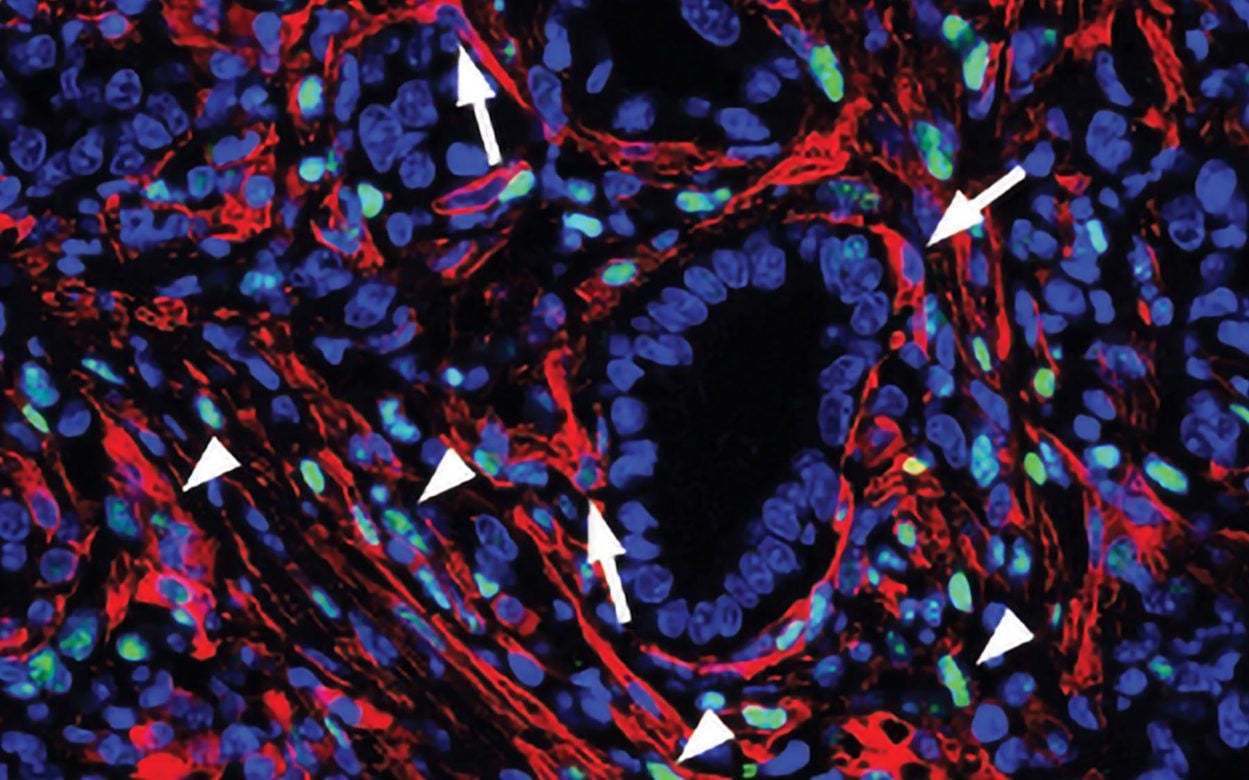

Turning cells against pancreatic cancer

Cold Spring Harbor, NY — Pancreatic cancer has a grim prognosis. It is usually detected after the disease has spread, and chemotherapy tends to do little to slow the cancer’s growth. Even with treatment, most patients live only about six months after they are diagnosed with the disease. Researchers in Professor David Tuveson’s laboratory at … Continue reading Turning cells against pancreatic cancer